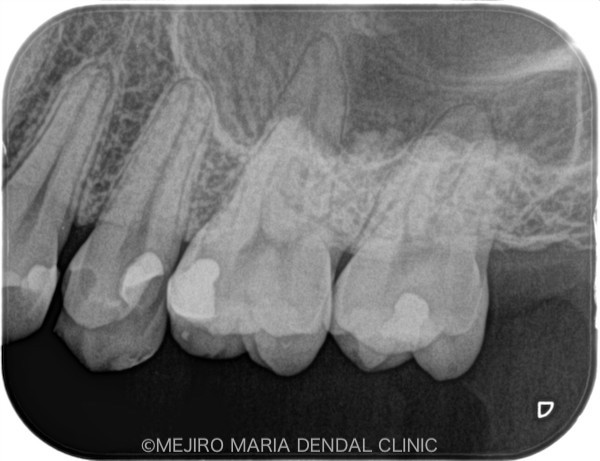

による歯髄保存症例(精密根管治療)_レントゲン_治療前1.jpg)

赤丸は近接しているう蝕(虫歯)箇所

患者様は、他院にて虫歯治療をおこなった際に、「虫歯が深くまで進行しており、神経の処置(根管治療)が必要です」と説明を受け、当院へ来院されました。虫歯の治療箇所には、治療前には痛みや違和感はなく、患者様は「なぜ神経の治療が必要なのか?」と疑問に思われていました。

当院での診査の結果、前の歯科医院で処置をした後だったために、正確な診断までには至りませんでしたが、「可逆性歯髄炎」と診断し、この歯の神経は保存できると判断しました。